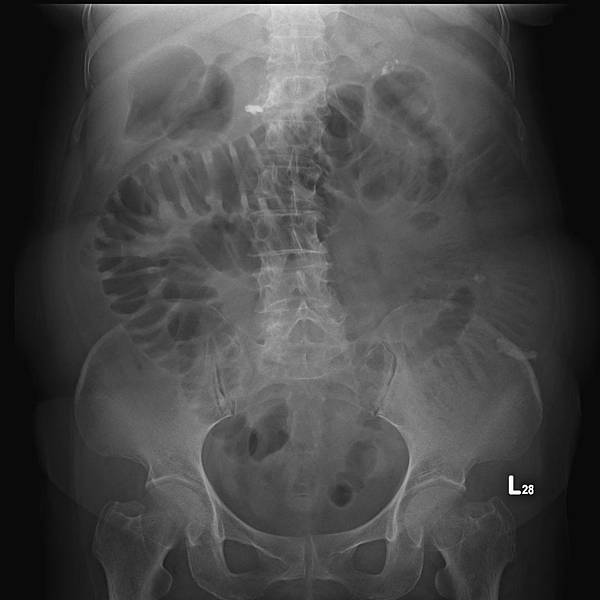

KUB看不出她的病有多嚴重:

72歲女性,乙狀結腸(黃箭頭)充滿糞便,但她會告訴你,她每天都有解便。如上圖所示,這樣的病例,病人直腸(藍箭頭)糞便清得很乾淨。

如果KUB顯示大腸糞便不多,這種胃酸逆流怎麼治療?